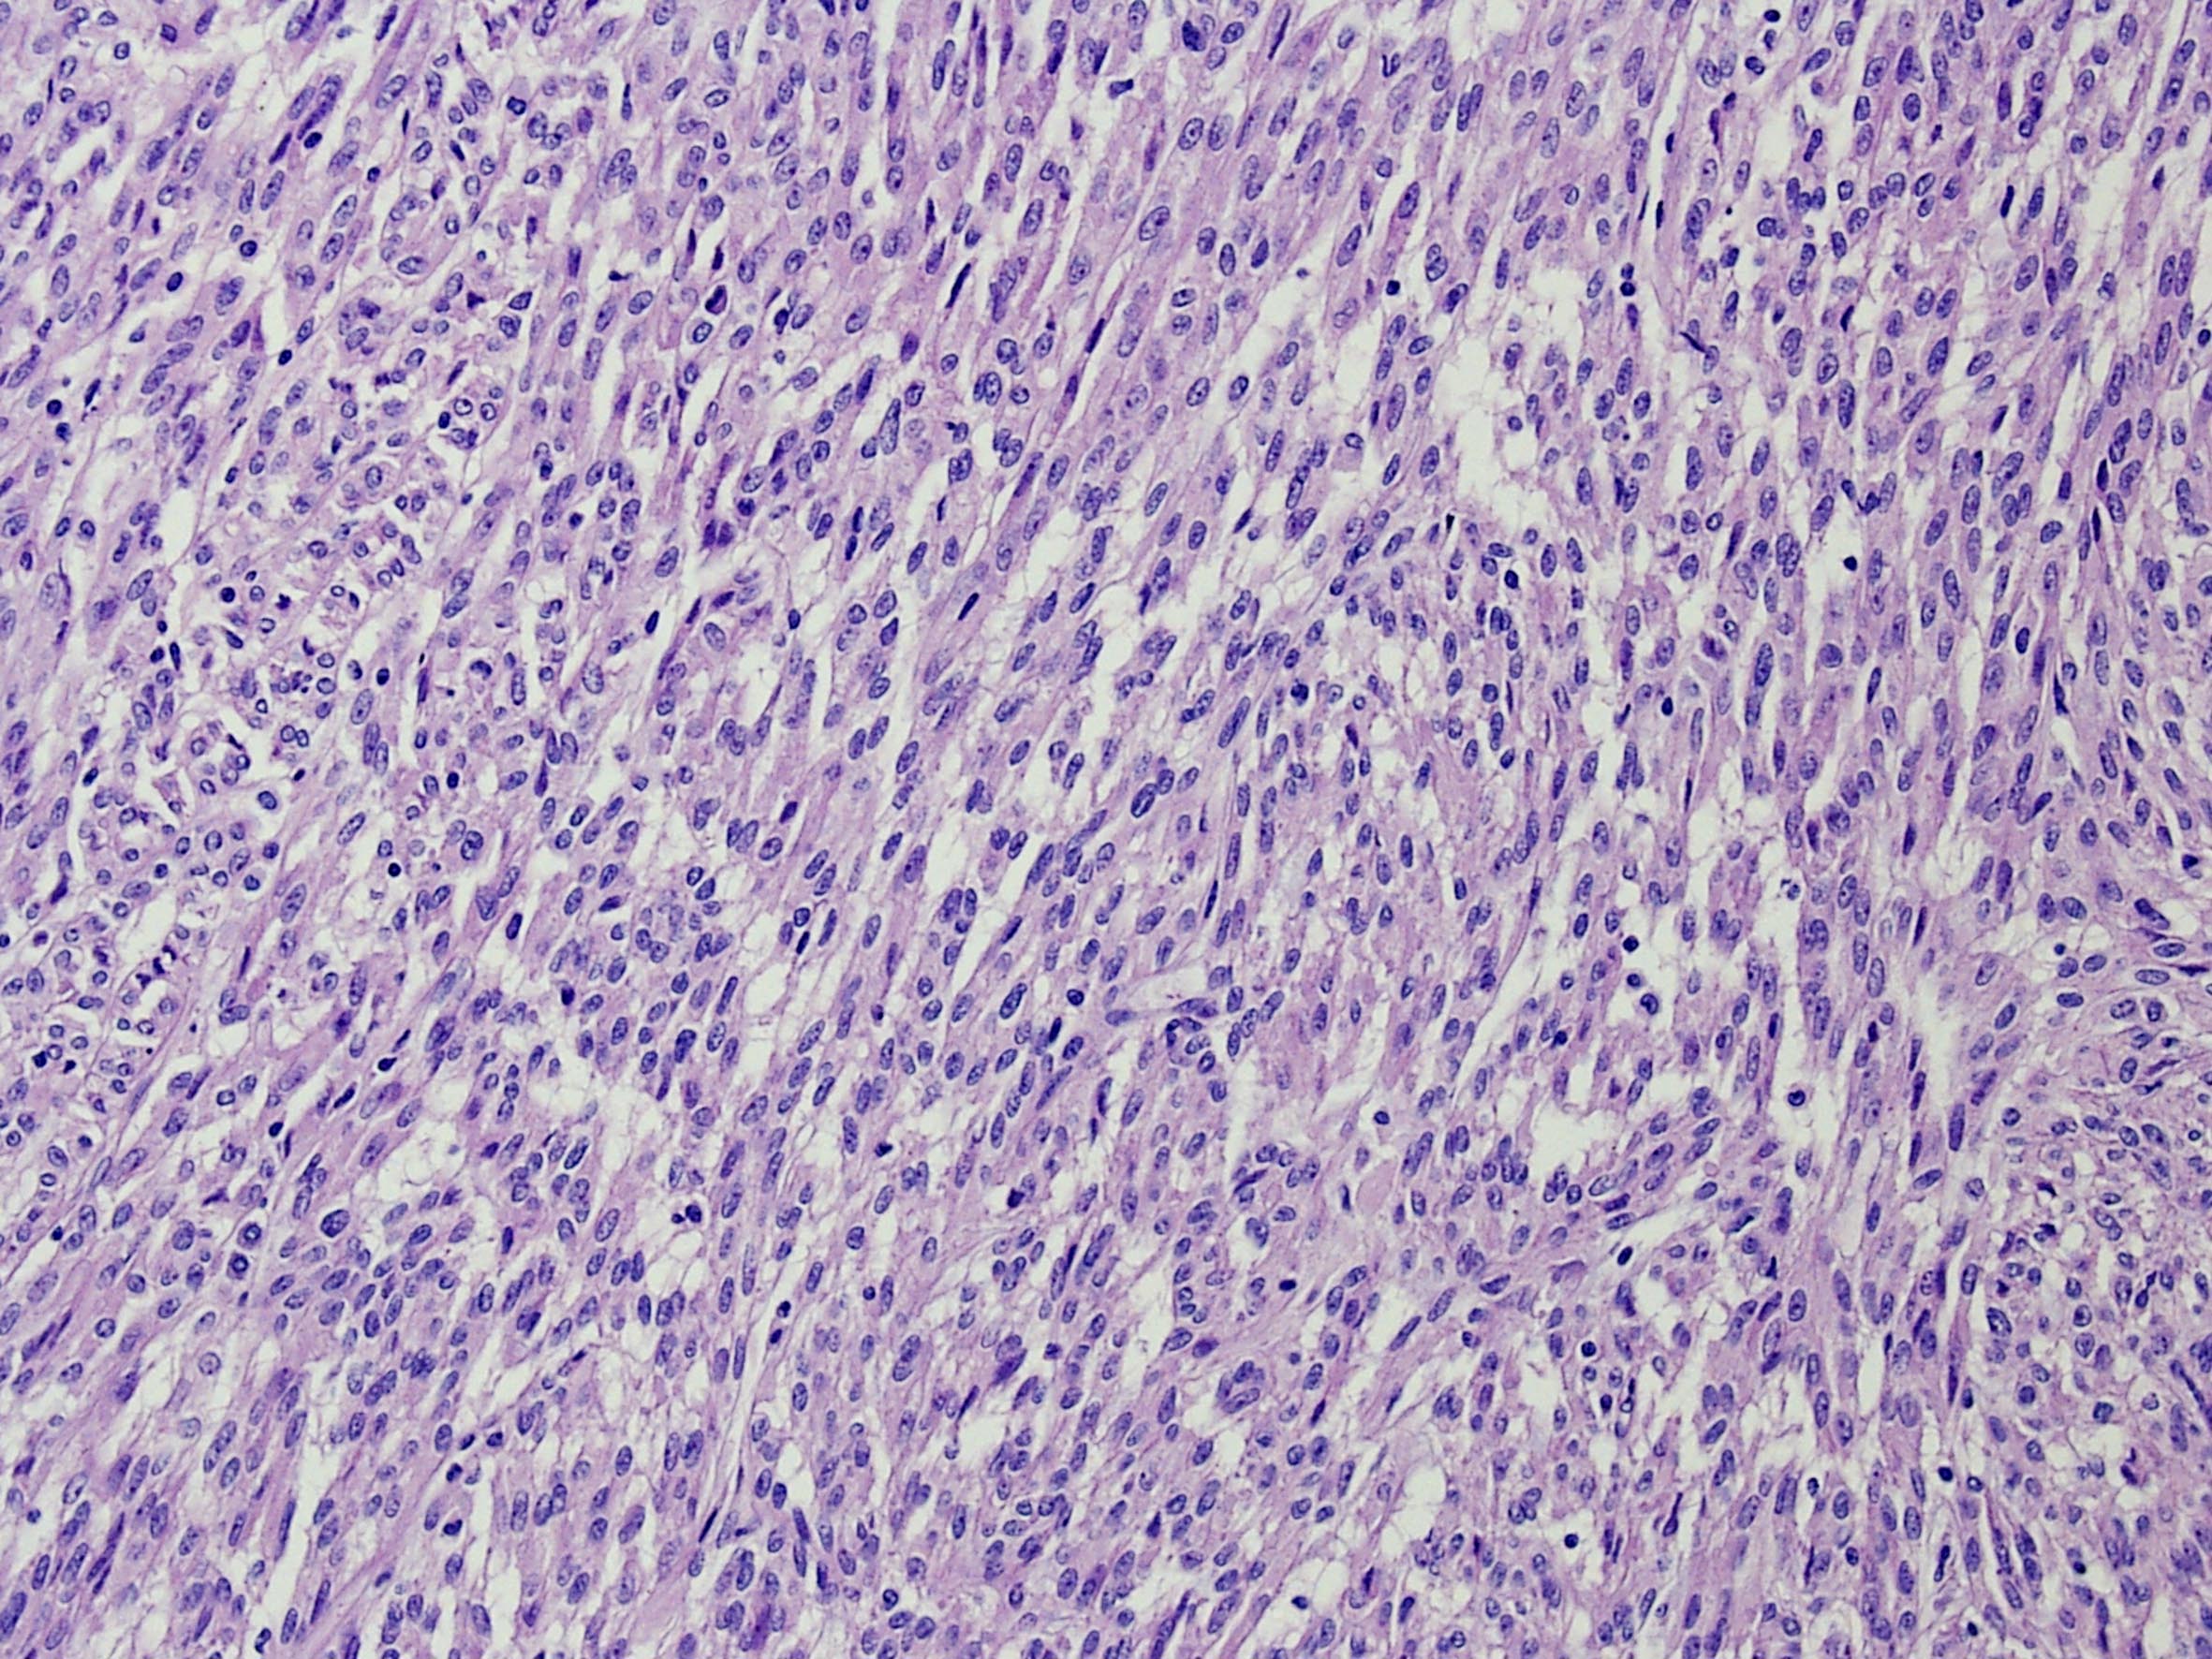

Classification of renal tumors

Case ID: 266